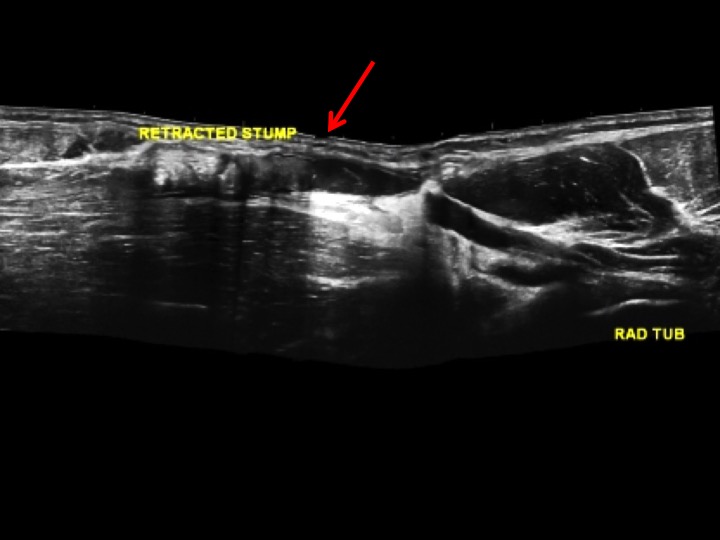

As is standard practice in the States, our US techs scan the patients and then review images with us. All too often (maybe because we are too busy, or maybe because were not entirely comfortable with MSK US) many of us are quick to accept what the technologists show us and base our reports on what is conveyed by their image labels and their scan notes. My (most excellent) technologist was amazed by this case, where she demonstrated a complete tear at the biceps myotendinous junction, And then a separate complete tear through the distal tendon. That made no sense. I needed to prove it and document the tear site. Slide 3 is the extended FOV showing the complete distal avulsion of the tendon off the radial tuberosity, retracted to the upper arm. The redundancy of the markedly retracted tendon created the confusing image (similar injury on MRI slide 4). Since the diagnosis was obvious to the referrer, our only job was to identify the site of the tear and the length of the defect. If we couldt get that right, wed have been utterly useless.